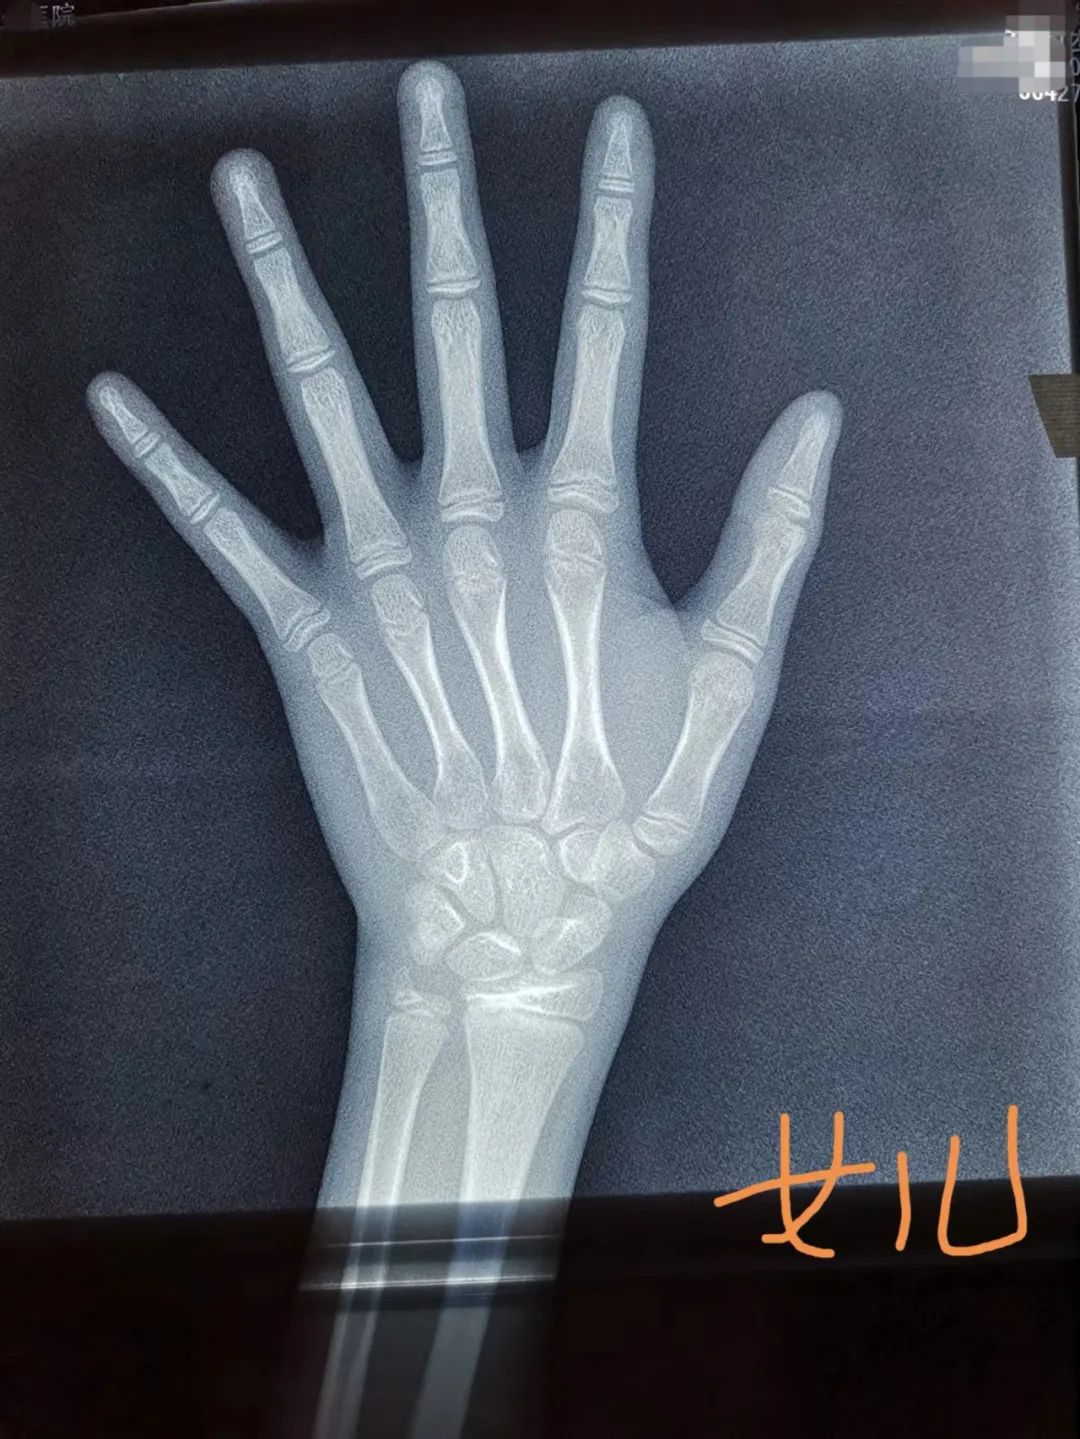

拍了三次骨龄片

10周岁那年,虽然两个孩子长得蛮好,在班上身高属于中等,但他们还是带孩子去了一家医院的儿科门诊,主动跟医生说要拍骨龄片。“主要是想看看骨龄有没有超前,能不能长到我们希望中那样高。”何女士说。

拍了骨龄片,测了父母和孩子的身高,最后电脑里吐出一张身高预测表,显示儿子终身高176.4厘米,女儿终身高157.7厘米。

半年后,何女士按照专家的要求,去复查,又拍了骨龄片。当时儿子身高155.2厘米,女儿146.9厘米,但这次预测的终身高降了:儿子175.9厘米,女儿154.7厘米。

“听医生说我儿子骨龄超了1.2岁,女儿超了0.5岁,一下又焦虑起来了。”何女士说。

黄轲主任医师说,最近门诊里最多的是来看身高的,其次是性早熟。前两天,门诊里来了对母子,妈妈有些焦虑。“医生,我儿子是不是性早熟了?以后是不是长不高了?”只见她翻出儿子的骨龄报告说,儿子今年11周岁,前不久刚拍了骨龄片,显示骨龄已13岁左右,当地医生说孩子的骨龄偏大了2岁,怀疑是性早熟。

黄轲主任看了孩子的骨龄片,又给孩子做了体格检查,孩子身高150厘米,偏胖,但睾丸还没有发育,没有出现性发育的迹象,不需要药物干预治疗。

“一般来说,在孩子发育早期,骨龄生长先启动,然后再是身高快速增长,最终两者持平。骨龄先于身高增长,很多孩子在发育早期,骨龄都是提前的。因此,不能单看一次骨龄情况来判断孩子的发育情况。在这个特殊时期,如果进行药物干预,不一定能得到很好的获益。” 黄轲说。

单凭骨龄并不能准确预测身高

不推荐常规检测骨龄

“不少家长不管孩子什么情况,到了门诊开口就要求给孩子先测个骨龄,但并不是每个孩子都有必要做骨龄检测。门诊中,真正需要测骨龄的大约只占2/3。也就是说,约有1/3的孩子无需做骨龄检测。”

黄轲主任医师说,经过评估,认为有性早熟、矮小或者和同年龄段正常的平均身高相差较大等异常情况的,才需要做骨龄检测。

“在门诊中,我们也碰到过一些家长,孩子只有两三岁,而且身高发育在正常平均水平范围内,也带着来测骨龄,这也是不科学的。因为低年龄段儿童正常骨发育存在较大的变异性,骨龄评估诊断价值有限,因此,6岁以下儿童不推荐常规检测骨龄。”

骨龄不是预测身高的唯一标准,不能单凭骨龄来判断孩子的终身高,遗传、营养、内分泌激素、疾病、生活环境等因素,都会影响终身高。

“目前骨龄可用于预测成年身高,但并没有任何一种方法能精确预测成年身高,其结果存在很大差异。”

影响骨龄的因素有很多,比如性早熟的孩子,下丘脑垂体被激活,激素水平上升,在雌激素的刺激下,骨龄进展会非常快,当骨龄进展速度超过年龄,就会导致身高的丢失。此外,肾上腺分泌的激素水平,也会促进骨龄进展。

黄轲认为,不能夸大了单次骨龄对身高预测的作用。尽管骨龄的规律性变化能比较好地反映儿童体格发育情况和生长潜力,但由于骨骼发育除受遗传因素影响外,也受到内分泌激素、炎症、营养状态、某些药物、应力作用等多因素影响,导致骨龄的进展呈现连续性、非匀速性、个体性的特点,因此单次骨龄检测只能反映该检测时间节点的发育状况,据此预测未来身高并不科学。